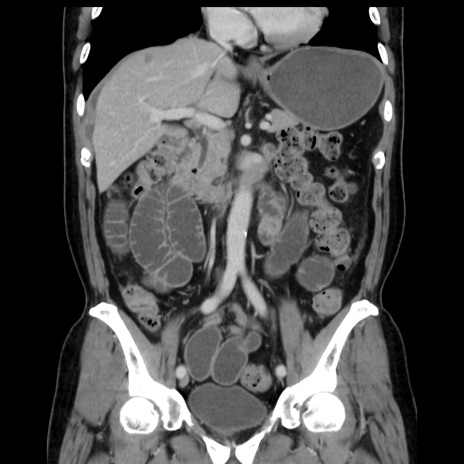

症例16(冠状断像)

【症例】 70歳代男性

【主訴】 腹痛、嘔吐

【現病歴】 約1ヶ月前より間欠的に腹痛と嘔吐あり、当院消化器内科を受診したところCTで多発する肝臓のLDAを指摘され、精査中であった。以降は消化器症状は安定していたが、2日前より嘔気と腹痛があり、同日より排便・排ガスが消失した。改善認めず、 本日、救急外来を受診した。

【既往歴】 大腸ポリープ切除後。

【身体所見】意識清明・会話良好、BT 36.3℃、BP 127/80mmHg、 P 80bpm、腹部:膨満あり、平坦・軟、上腹部正中および下腹部正中に圧痛あり、反跳痛なし、筋性防御なし。

【データ】WBC 7200、CRP 0.77